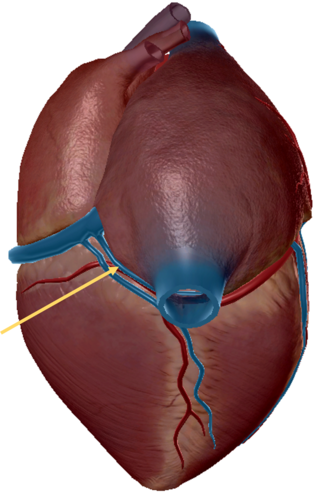

anterior inter ventricular sulcus

right coronary artery

circumflex artery

great cardiac vein

middle cardiac vein

coronary sinus

anterior inter ventricular artery

posterior interventricular sulcus

small cardiac vein